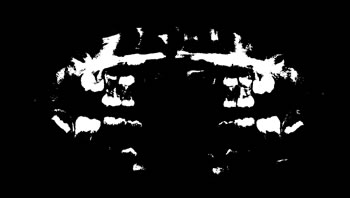

Figure 4: Annotation of the teeth.

Image annotation

The process of annotating the images of our proposed data set occurred in two parts. First, it was initiated by the upper jaw through the annotation of the third right upper molar and making the annotation of all the teeth of the upper arch to the third left upper molar. Then, the same process was performed on the lower jaw with all the teeth, and in the same direction as the upper jaw, from left to right, starting with the annotation of the third right lower molar, and annotating all teeth from the lower arch to the lower third molar. Figure 4 illustrates the tooth annotation process through a panoramic X-ray image of the data set.